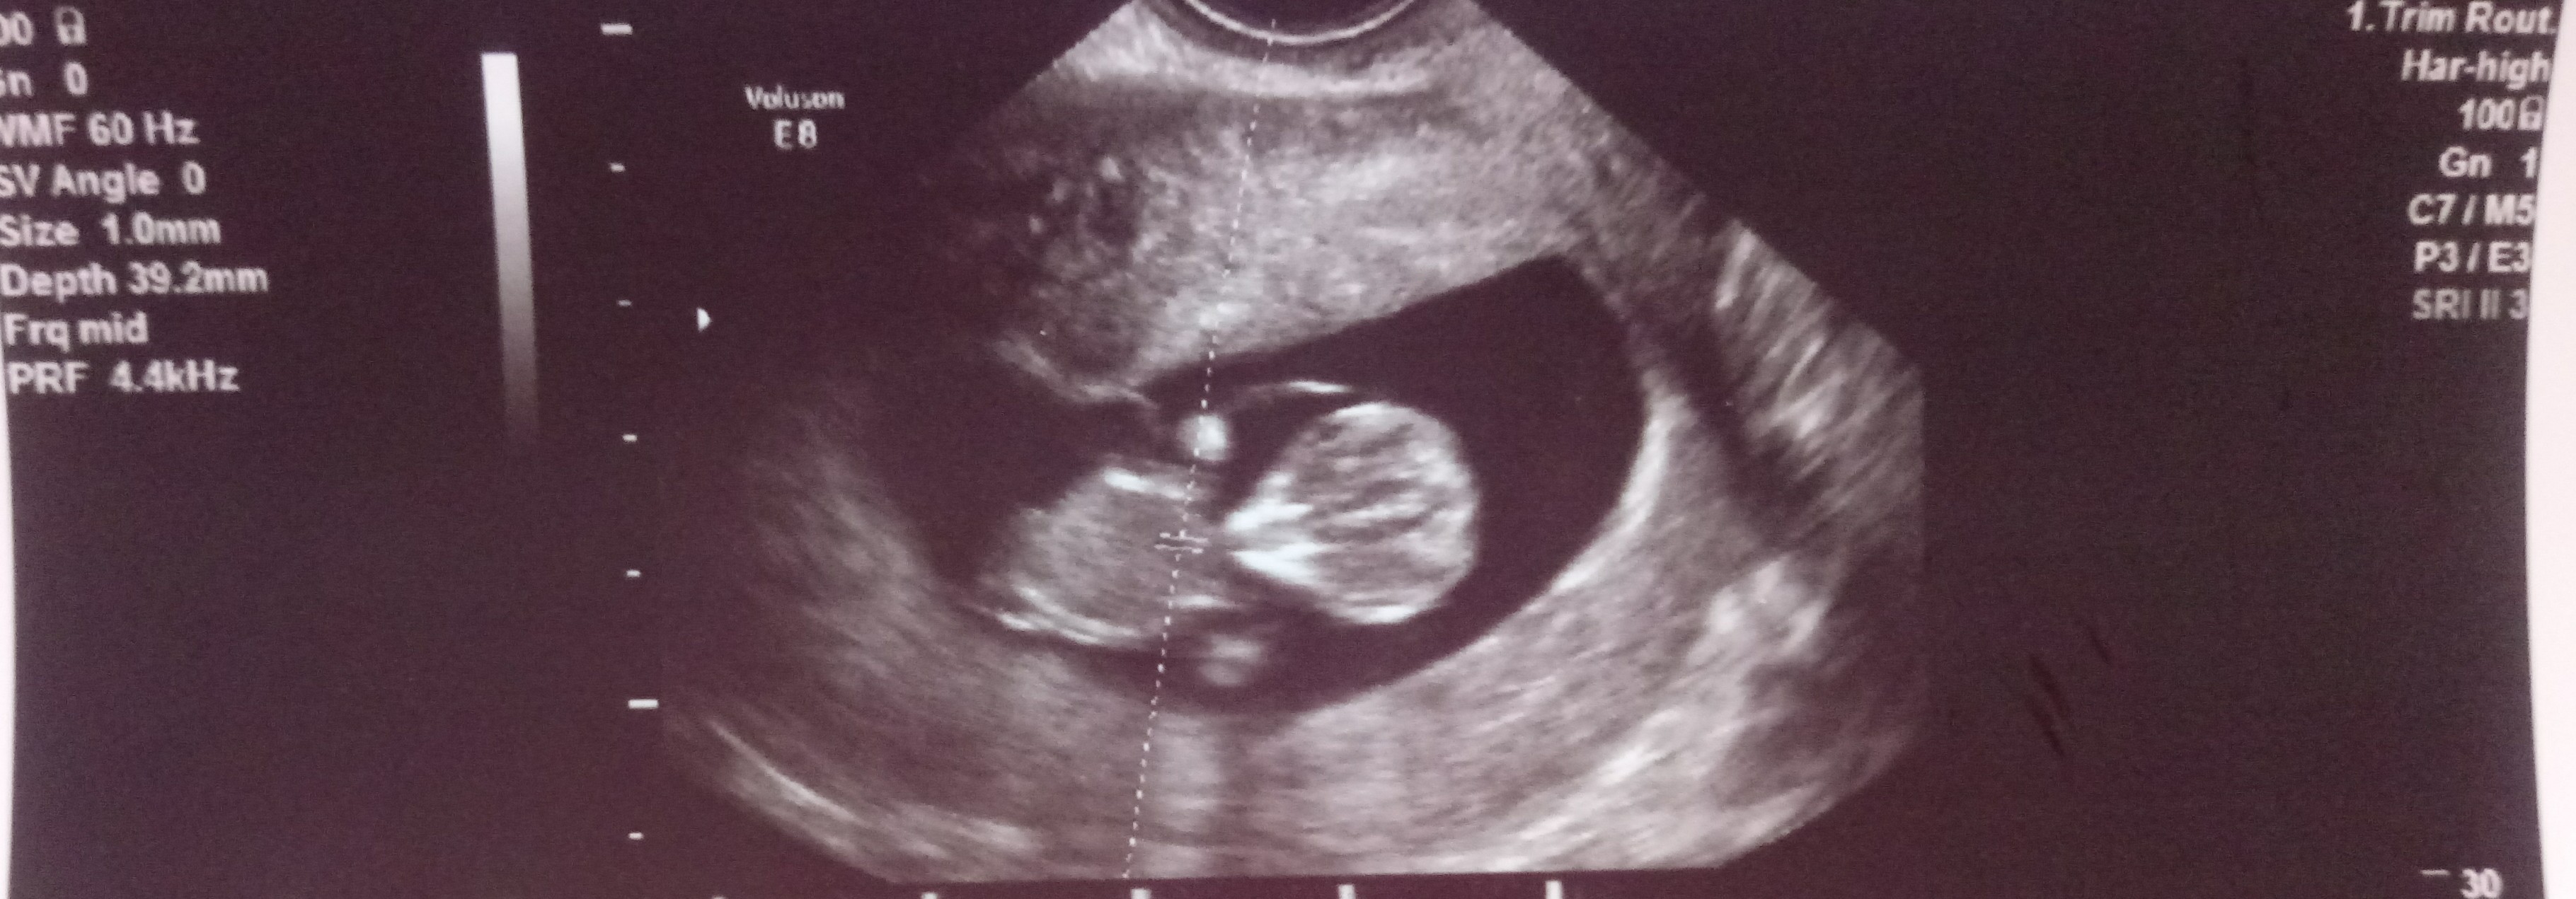

A dziękuję za pamięć [emoji173]️. Udanego urlopowania [emoji4]Karolina przechodziłem przez 15 stron bo dzisiaj będąc na urlopie przypomniało mi się ze miałaś w Piatek mieć wyniki!! Gratulacje Kochana to super duper wieści!